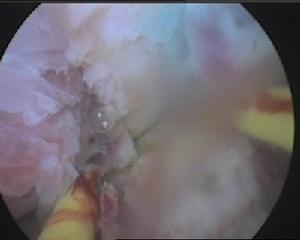

近年來較為常用,既可觀察宮腔內形態,明確有無縱隔及縱隔類型,又可在鏡下切除縱隔,達到治療目的。